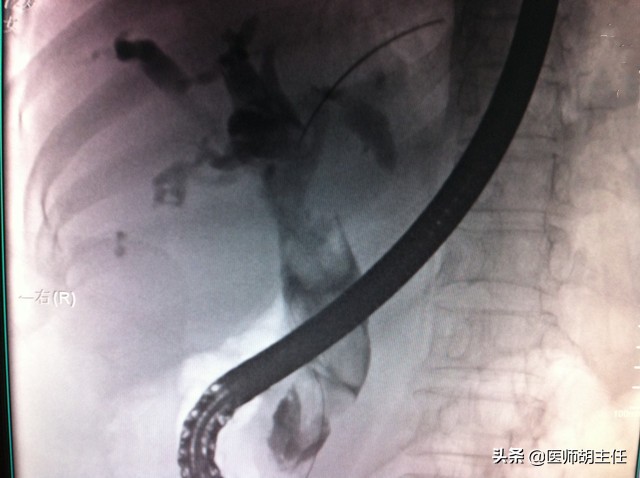

自身免疫性肝病: 包括肝炎、原发性胆汁性胆管炎/PBC及原发性硬化性胆管炎/PSC。 此病特点是血清中可检出自身抗体。因为是免疫机制障碍所致,故影像学检查对自身免疫性肝炎没有太大作用;对PBC而言,可用于同其他病鉴别或者病情进展至肝硬化时查看是否有门静脉高压,但都对明确诊断无直接帮助; 对PSC, 经内镜逆行性胆管造影是最适用的手段,超声可以帮助观察肝内、胆管壁等情况,此型上, 超声的作用大于CT。